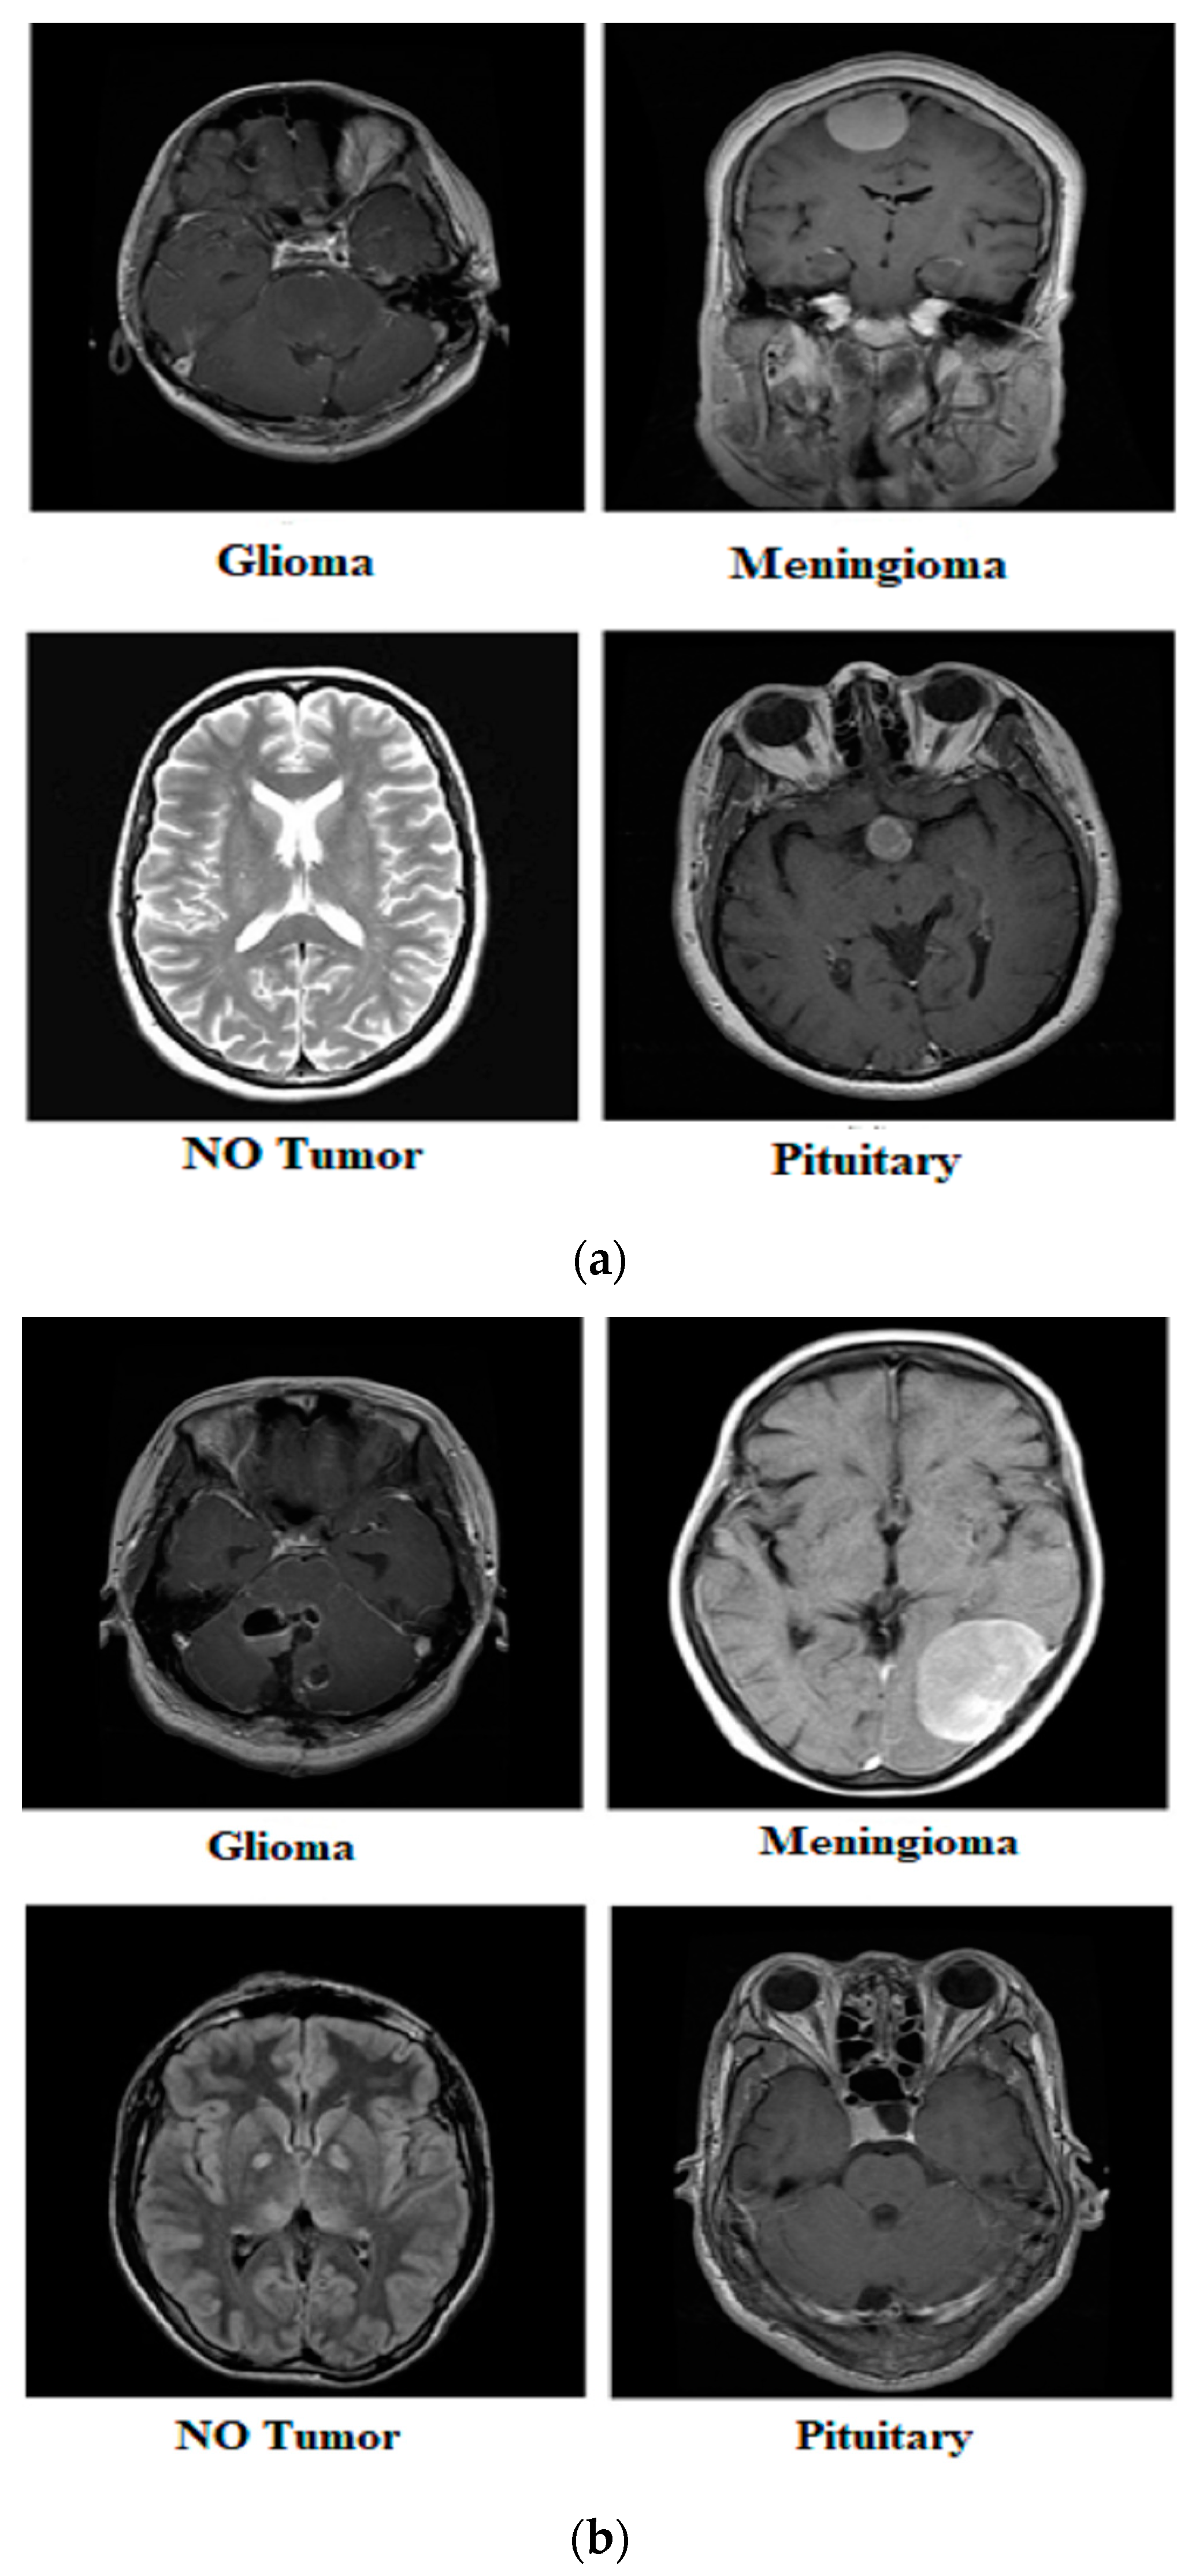

3.1. MRI Dataset

| Class | Images | Train | Test | Class | Images | Train | Test | Class | Images | Train | Test |

| Glioma | 1621 | 1321 | 300 | Yes | 155 | 135 | 20 | Yes | 1500 | 1200 | 300 |

| Meningioma | 1645 | 1339 | 306 | No | 84 | 66 | 18 | No | 1500 | 1200 | 300 |

| Pituitary | 1757 | 1457 | 300 | ||||||||

| No Tumor | 2000 | 1595 | 405 | ||||||||

| Total | 7023 | 5712 | 1311 | Total | 239 | 201 | 38 | Total | 3000 | 2400 | 600 |